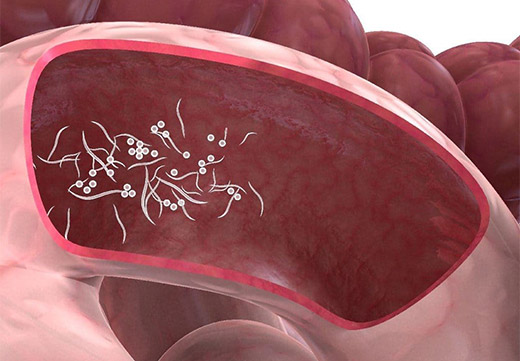

- Частые запоры. Происходит подобное, когда внутри тела присутствует большое количество глистов или они успели вырасти до крупных размеров. Перекрывается просвет кишечника, дефекация становится затруднительной.

- Диарея. Появляется в результате активного размножения паразитов. Расстройство стула вызывают химические вещества – продукты жизнедеятельности червей.

- Боли живота, вздутие. Говорит о наличии инфекции и сторонних веществ в тонком кишечнике.

- Частые запоры. Происходит подобное, когда внутри тела присутствует большое количество глистов или они успели вырасти до крупных размеров. Перекрывается просвет кишечника, дефекация становится затруднительной.

- Диарея. Появляется в результате активного размножения паразитов. Расстройство стула вызывают химические вещества – продукты жизнедеятельности червей.

- Боли живота, вздутие. Говорит о наличии инфекции и сторонних веществ в тонком кишечнике.

- Аскариды. Заражение происходит при проглатывании яиц вместе с немытыми овощами, фруктами, водой, при поедании зараженной мухами пищей. Аскариды не имеют органов, отвечающих за прикрепление, постоянно перемещаются по телу хозяина. Излюбленное место локализации червей – тонкий кишечник, бывают случаи проникновения паразитов к другим органам. Человек, зараженный аскаридами, жалуется на боли в желудке и кишечнике, кашель, снижение аппетита, понос, кожную сыпь и зуд, раздражение, тревожный сон.

- Широкий лентец. Вид плоских ленточных червей. Крупный паразит человеческого организма, может достигать роста в 15 метров. Заражение происходит при употреблении в пищу рыбы с недостаточной термической обработкой. Человек ощущает сильные боли, тошноту, головокружение, слабость во всем теле и другие признаки недомогания.

- Карликовый цепень — тип ленточных червей. Основным носителем гельминтов выступает человек. Новый хозяин заражается через загрязненную почву, продукты питания, немытые руки. Длина карликового цепня не превышает 3 см. Пациент ощущает боли в животе. Наблюдается тошнота, рвота, нестабильный стул, головокружение. Глист отличается высокой токсичностью, лечение рекомендуется проводить в стационаре.